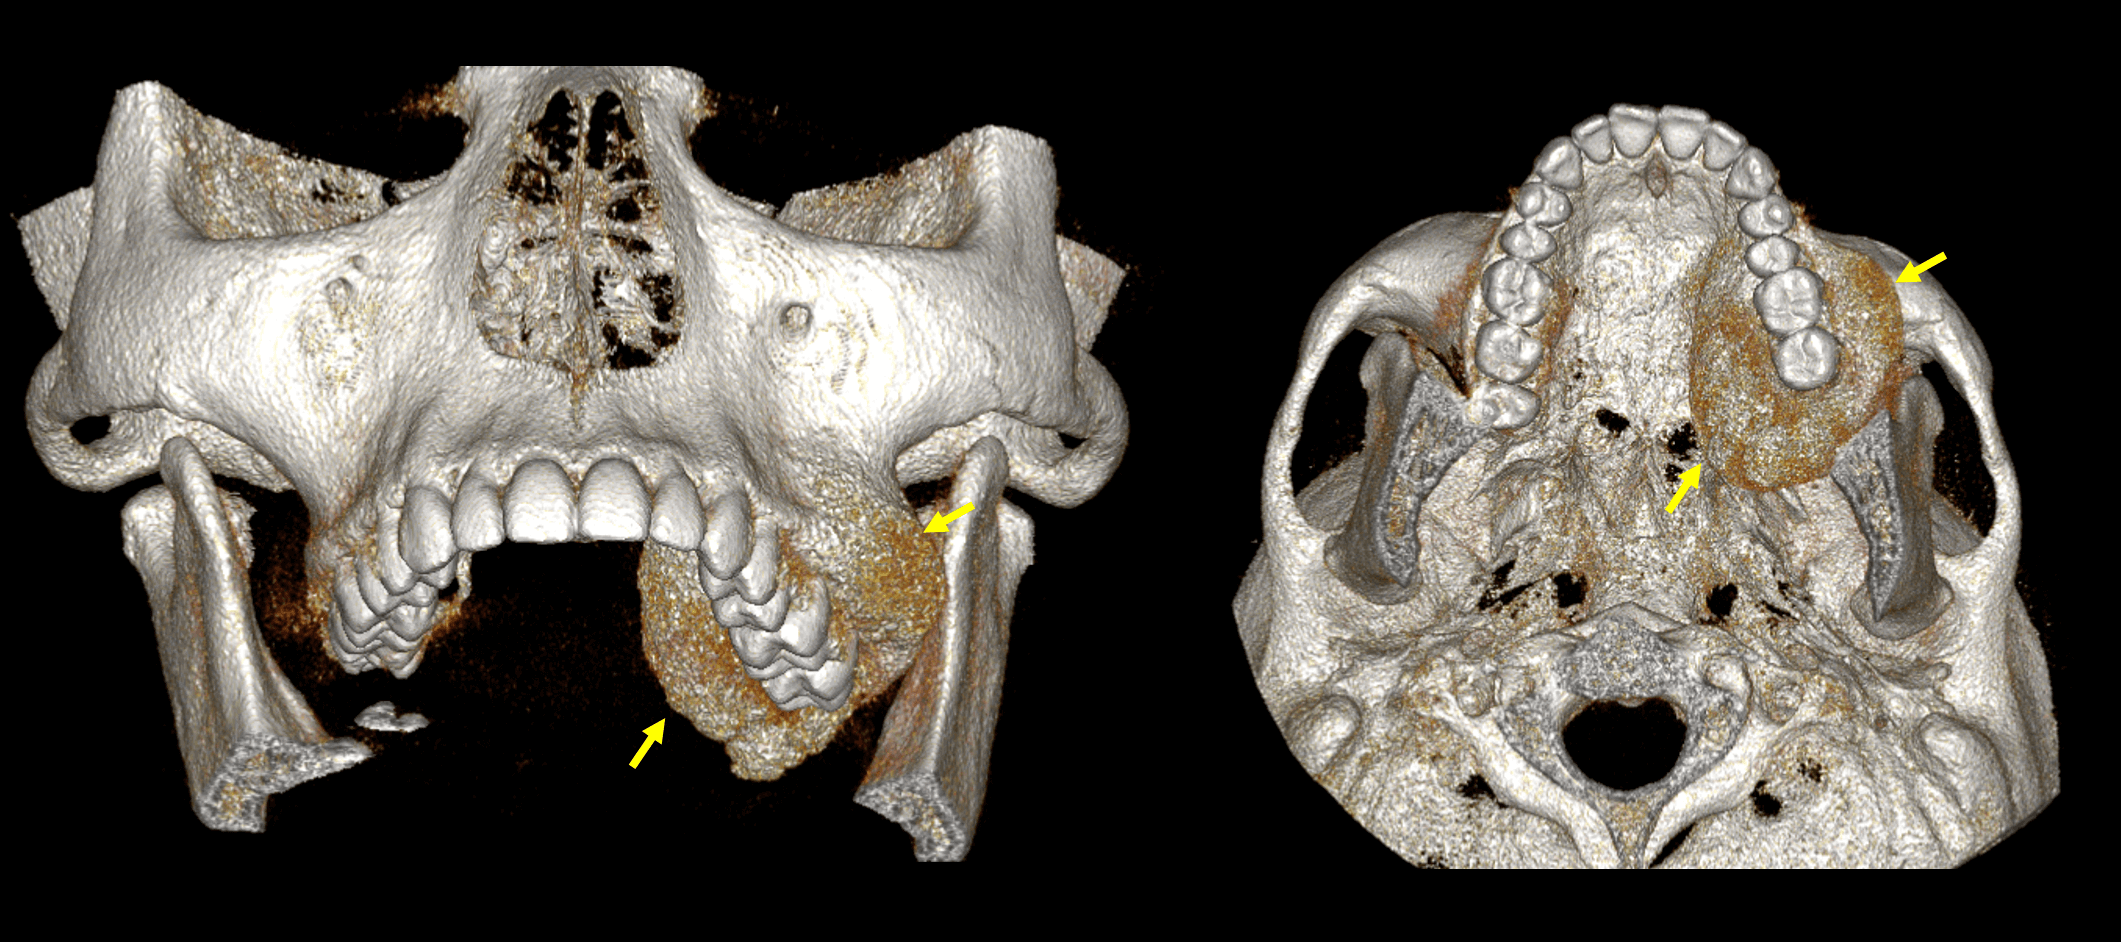

Fig.3

En cortes axiales (Fig,3) se observa la expansión en sentido medio-lateral de la lesion ósea y su extensión hacia el seno maxilar. SE evidencia que la lesion se expande de manera relativamente simétrica, también de forma posterior.

Fig.4

En la reconstrucción tridimensional (Fig.4) se observa el tamaño de la lesion ósea, donde se observa condicionando una marcada asimetría del hueso maxilar.